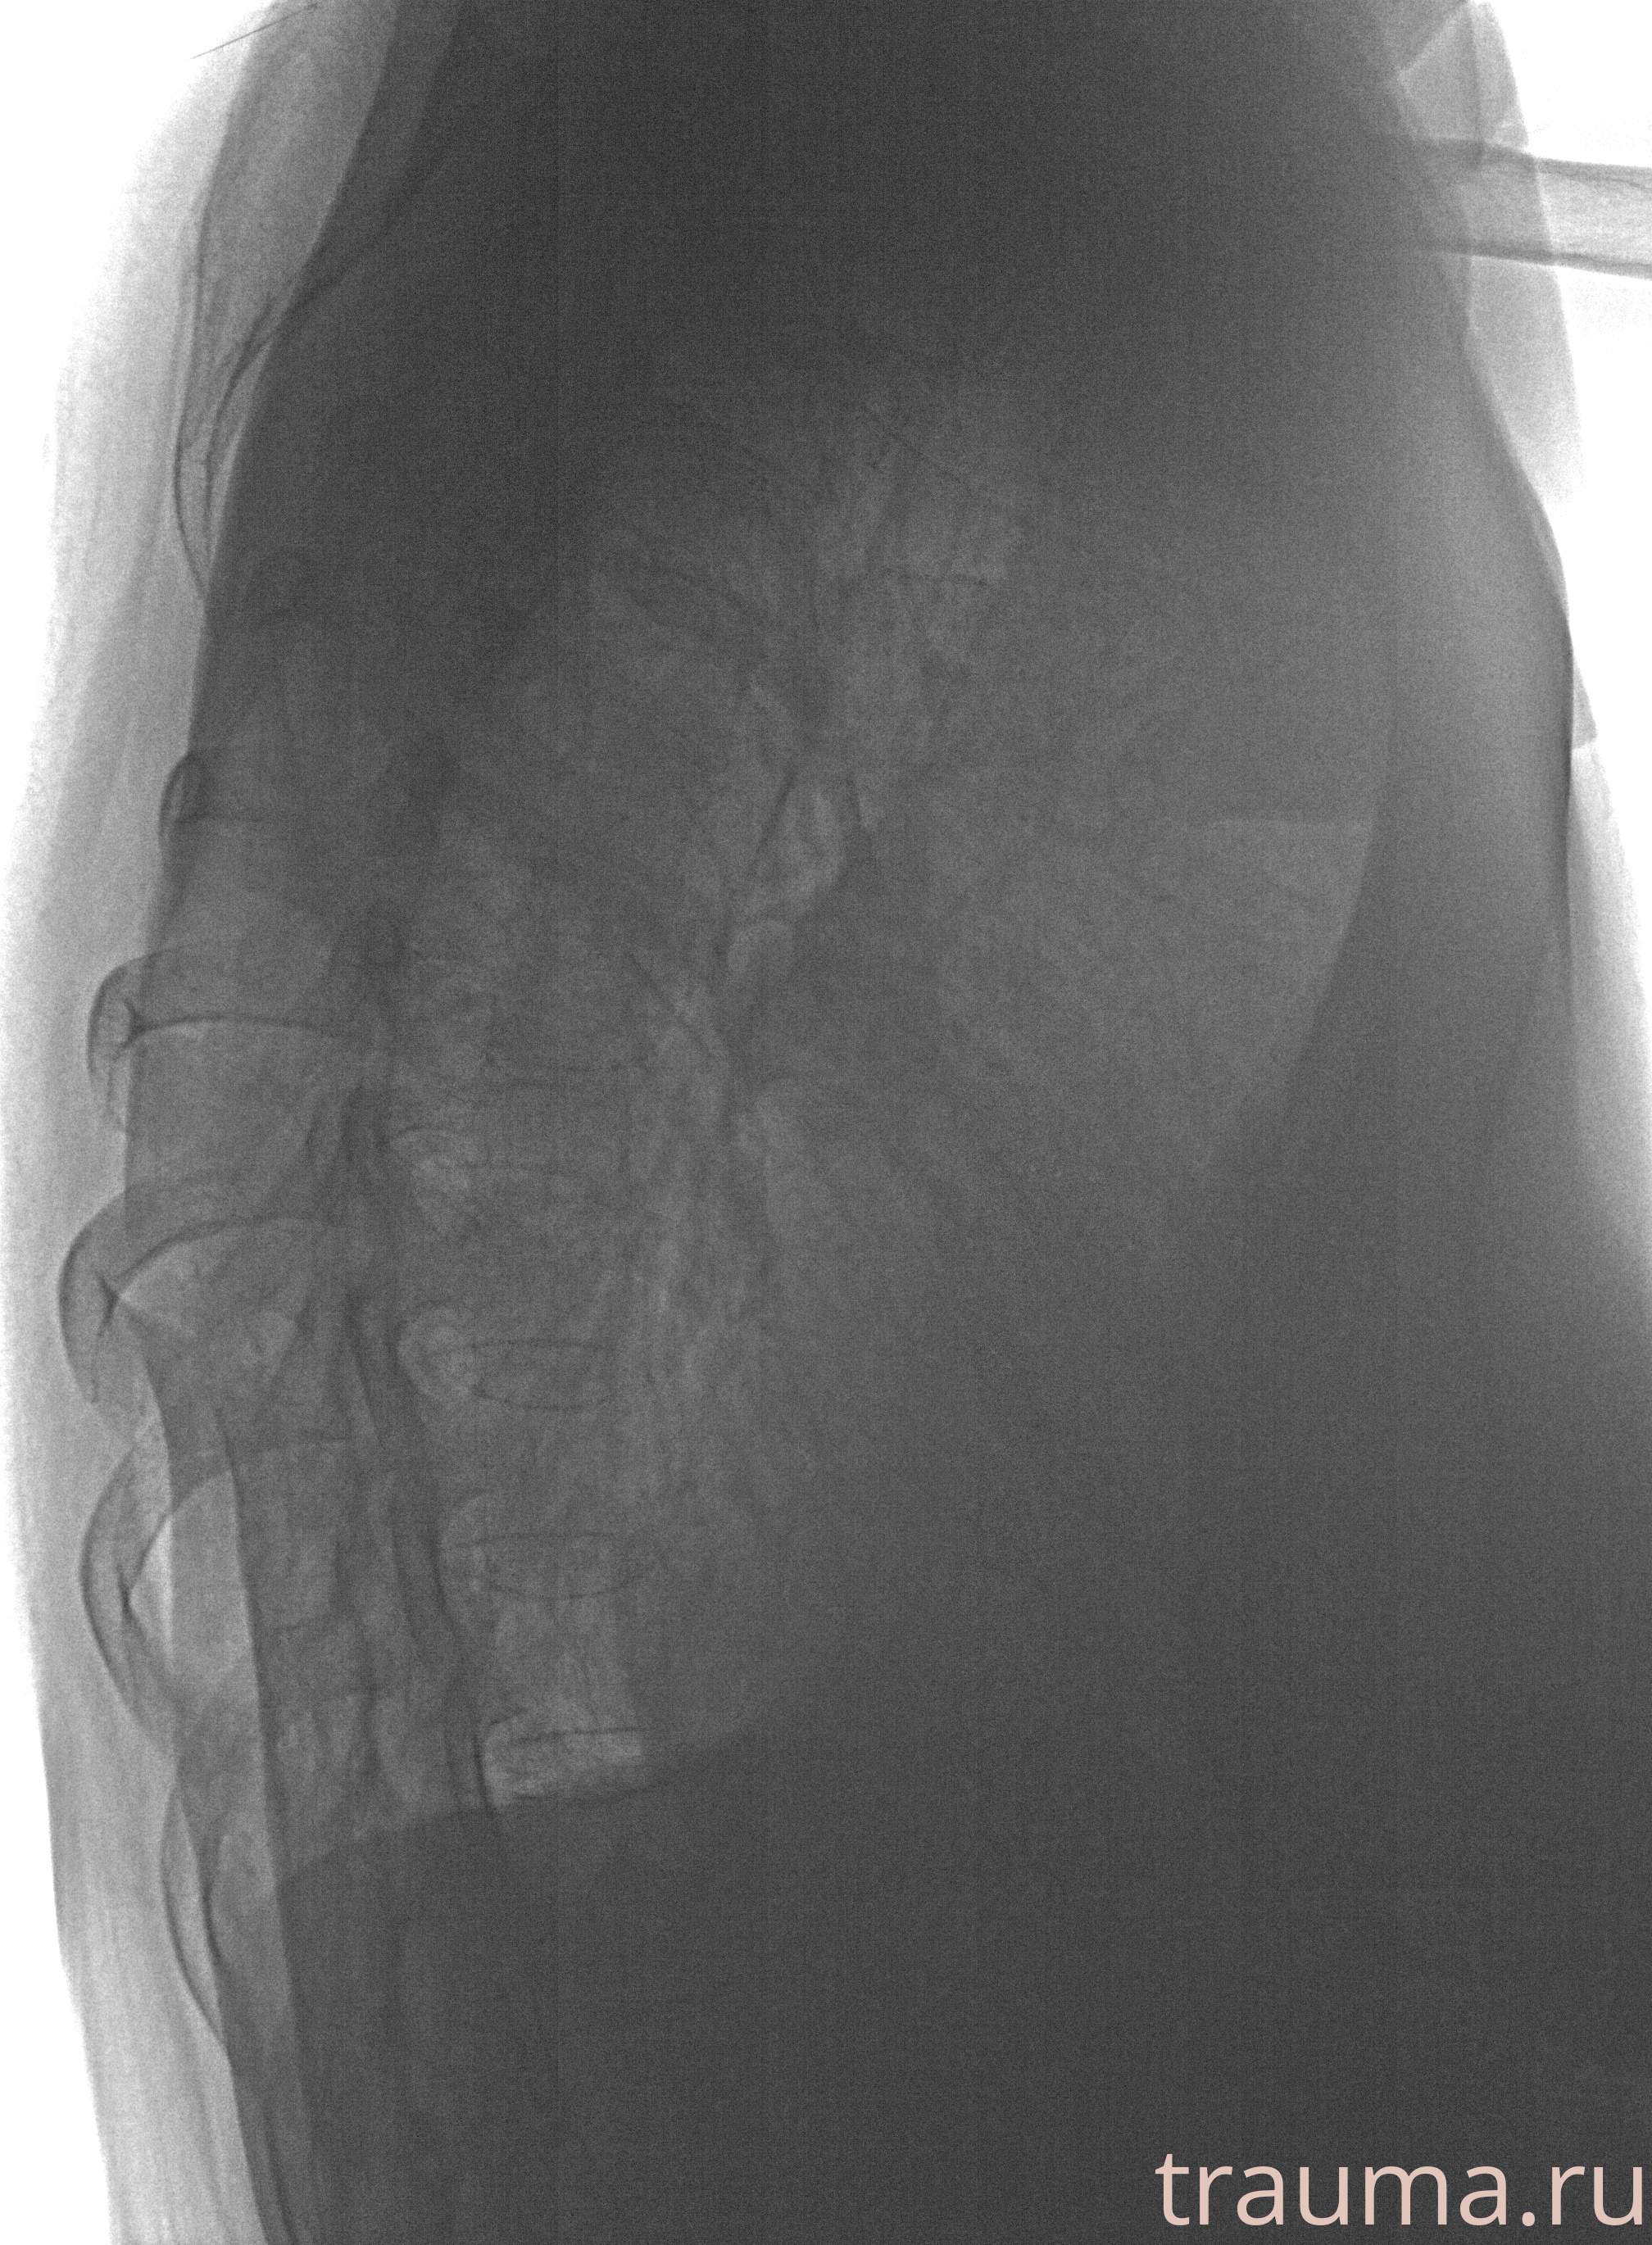

Рентген на дому: по вашему адресу приезжает врач-рентгенолог, травматолог-ортопед с мобильным рентгеновским аппаратом, проводит диагностику травмы или заболевания, делает необходимые рентгенограммы, дает рекомендации по дальнейшему лечению. Получить качественные снимки в домашних условиях возможно благодаря уникальной методике, разработанной МосРентген Центром для института  Склифосовского

при переломе шейки бедра и пневмонии от компании МосРентген Центр - партнера Института имени Склифосовского